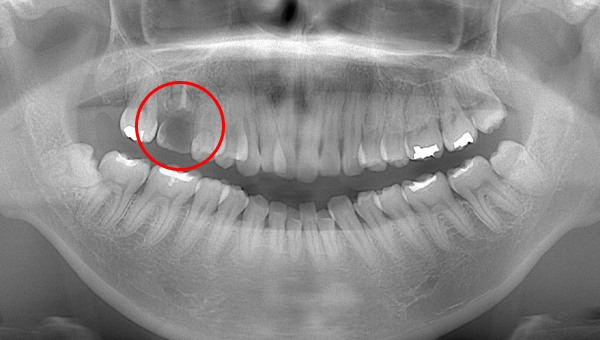

2021.4.3 定期検診時

この時はまだ症状がなかった

しかし歯は縦に割れており、いつ痛みが出てもおかしくないような状態であることは説明していた。

2022.1.15 根尖性歯周炎の急性化

疼痛ありで急患来院。

前々から爆弾抱えているような物で、何かあったら抜歯と伝えていた部位。以前よりクラウンマージン下で歯根縦破折であったが、症状なしで経過観察をおこなっていた。

抜歯予定とし、アモキシシリンとロキソニンを処方した。

2022.2.5 抜歯後の消毒

口腔内写真

CT画像

骨の状態はそこまで悪くないが、欠損が大きい。